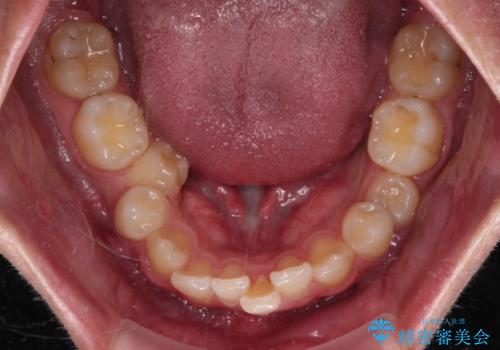

- 今回ご紹介するのは、

「全体的なデコボコ(叢生)」「上下の正中のずれ」 を主訴として来院された20代男性の患者様の症例です。

叢生が強く、歯が並ぶスペースが不足していたため、

上下左右の第一小臼歯を抜歯して、矯正治療のための適切なスペースを確保する計画としました。